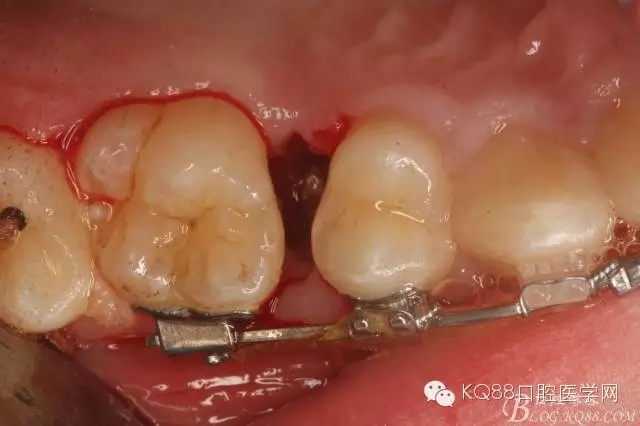

图8.因16与14合面的间隙仅2mm左右,牙根无法合向脱位,如何考虑15牙根的脱位将是最大问题。高速手机去除牙间隙内的覆盖在15牙根表面的牙龈组织

图10.去除牙龈组织后。露出15牙根断面,合面无法脱位